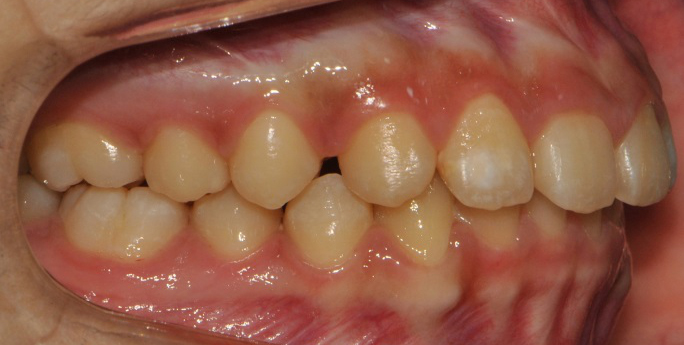

À§ ȯÀÚ´Â À´Ï°¡ ¾Æ·§´Ï¸¦ ³Ê¹« µ¤¾î¿ä(°ú°³±³ÇÕ) ¸¦ ÁÖ¼Ò·Î ³»¿øÇÑ ÃʵîÇлýÀ̾ú½À´Ï´Ù. ÅμºÀå ¾ÇÁ¤ÇüÀåÄ¡ »ç¿ëÈÄ È£ÈíÀÌ °³¼± µÇ¾úÀ¸¸ç Ä¡·áÀü¿¡ ºñÇØ ۰¡ 10cmÁ¤µµ ±Þ¼Ó ¼ºÀåÇÏ¿´½À´Ï´Ù.